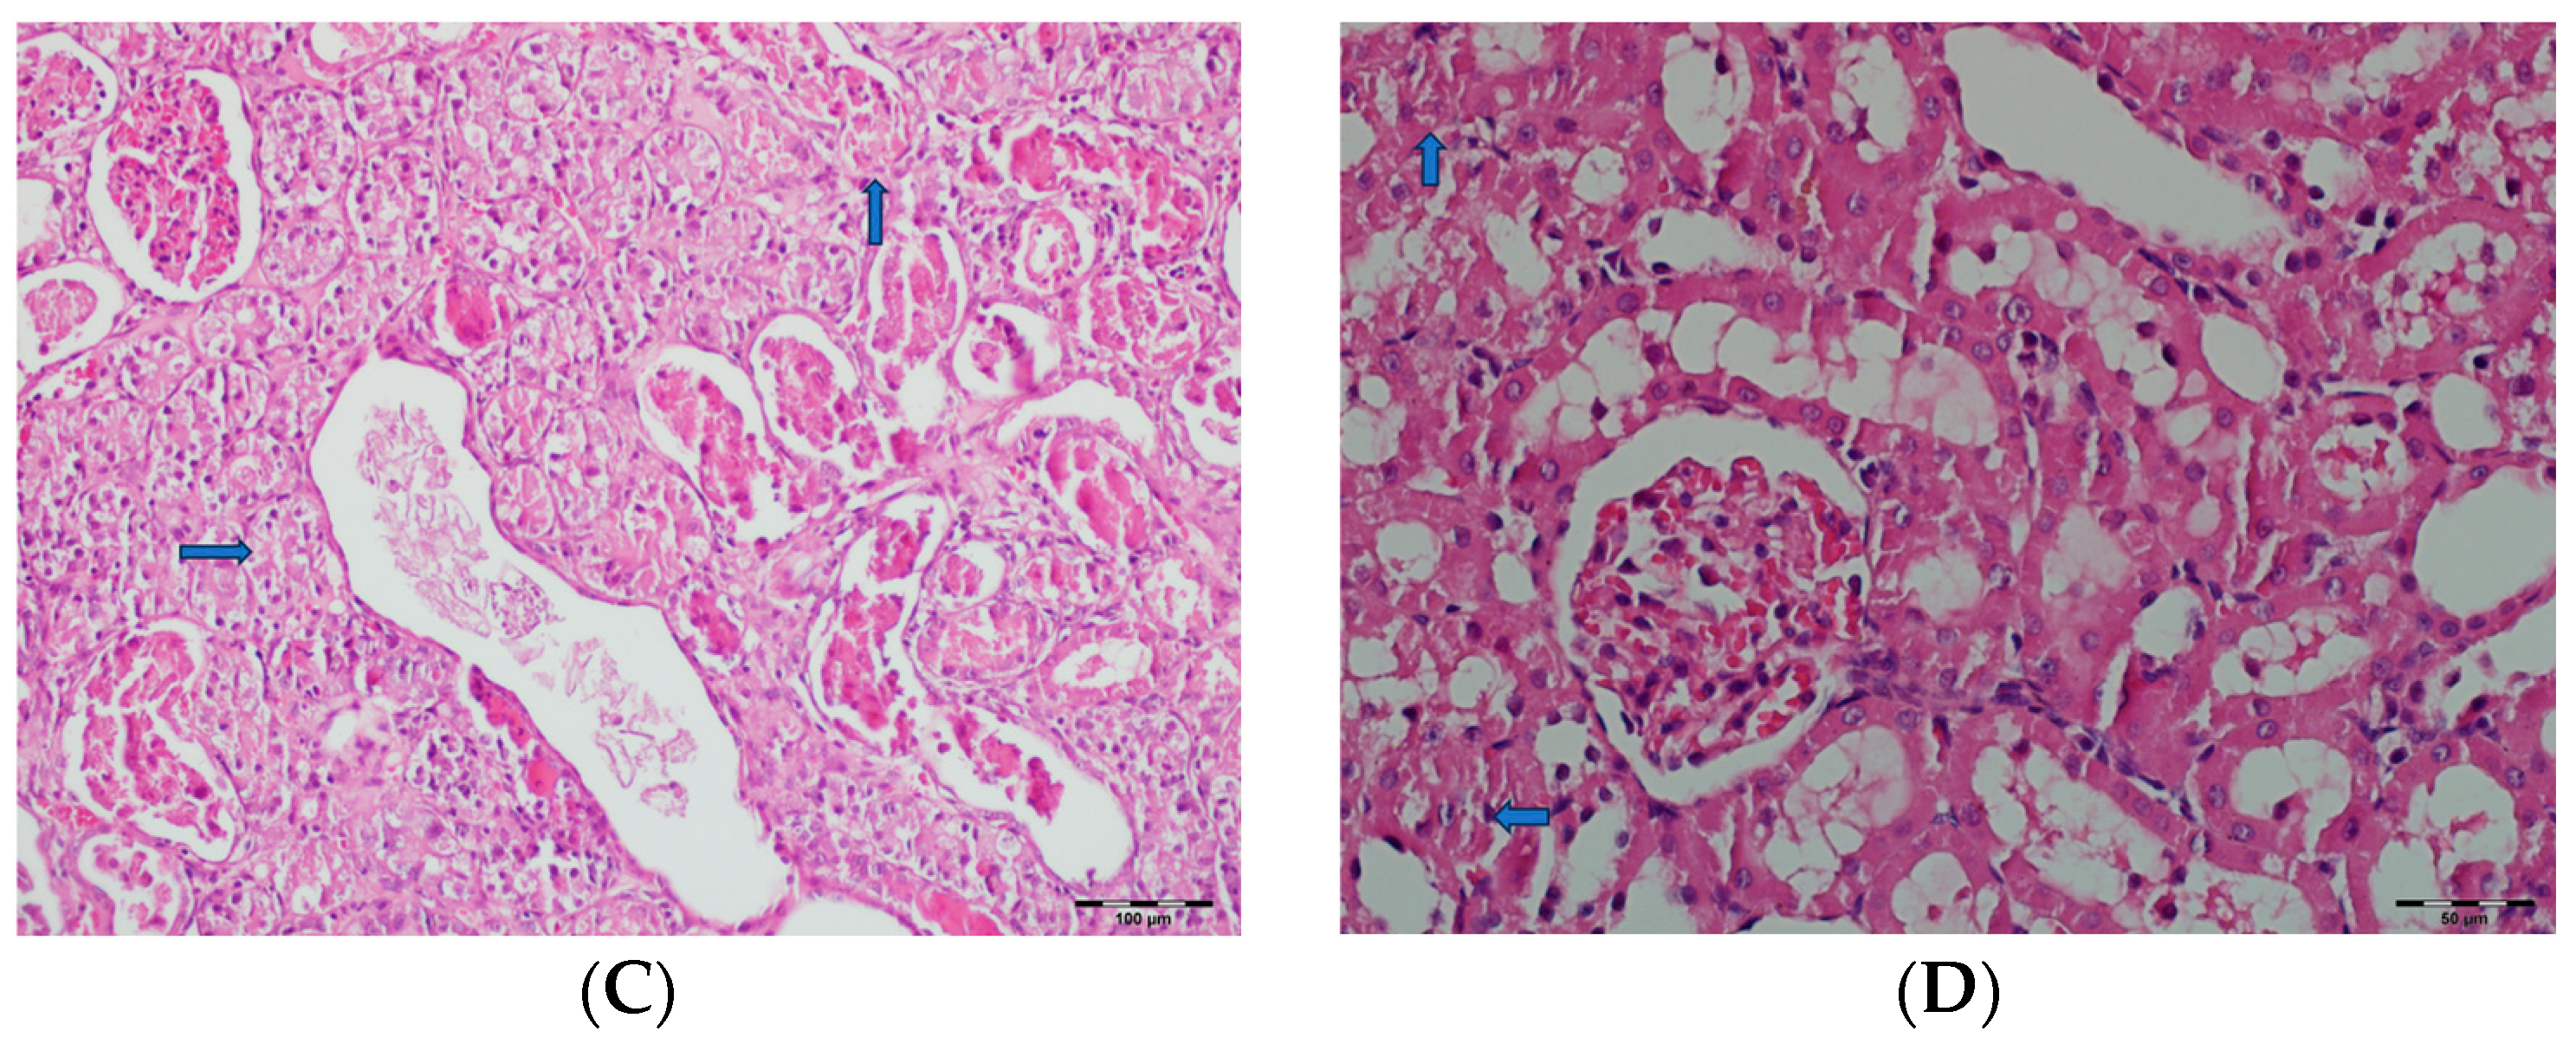

3.5. Histopathological Studies

- Bellos, I.; Pergialiotis, V.; Perrea, D.N. Kidney biopsy findings in vancomycin-induced acute kidney injury: A pooled analysis. Int. Urol. Nephrol. 2022, 54, 137–148. [Google Scholar] [CrossRef]